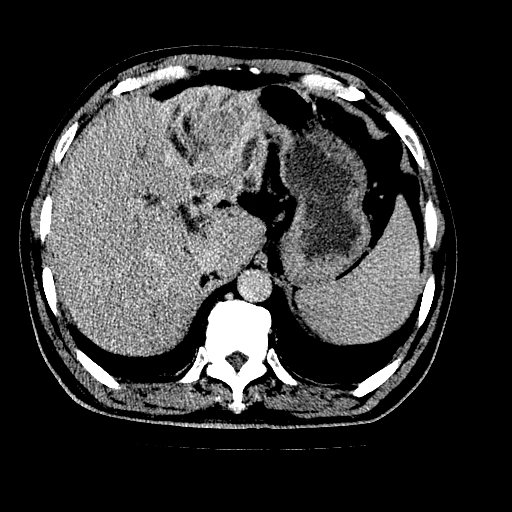

男,66岁,上腹部不适、黄染一周。彩超示:肝左叶占位,肝内胆管扩张,胆总管扩张,胆总管占位?

肝左叶不规则软组织肿块影,边缘不规整邻近肝实质受累分界不清;肝内胆管(左叶)明显扩张成“软藤状”,诊断:肝左叶胆管细胞癌。

肝左叶占位性病变,并胆管扩张,符合胆管细胞癌ct表现,门脉左支受累,左肾囊肿。窗宽太窄了,其他的看不清

左叶胆管细胞癌累及胆总管,门脉左支受侵,慢性胆囊炎胆结石,左肾小囊肿

肝左叶不规则软组织肿块影,边缘不规整邻近肝实质受累分界不清;肝内胆管(左叶)明显扩张成“软藤状”,诊断:肝左叶胆管细胞癌。胆囊钙乳症。